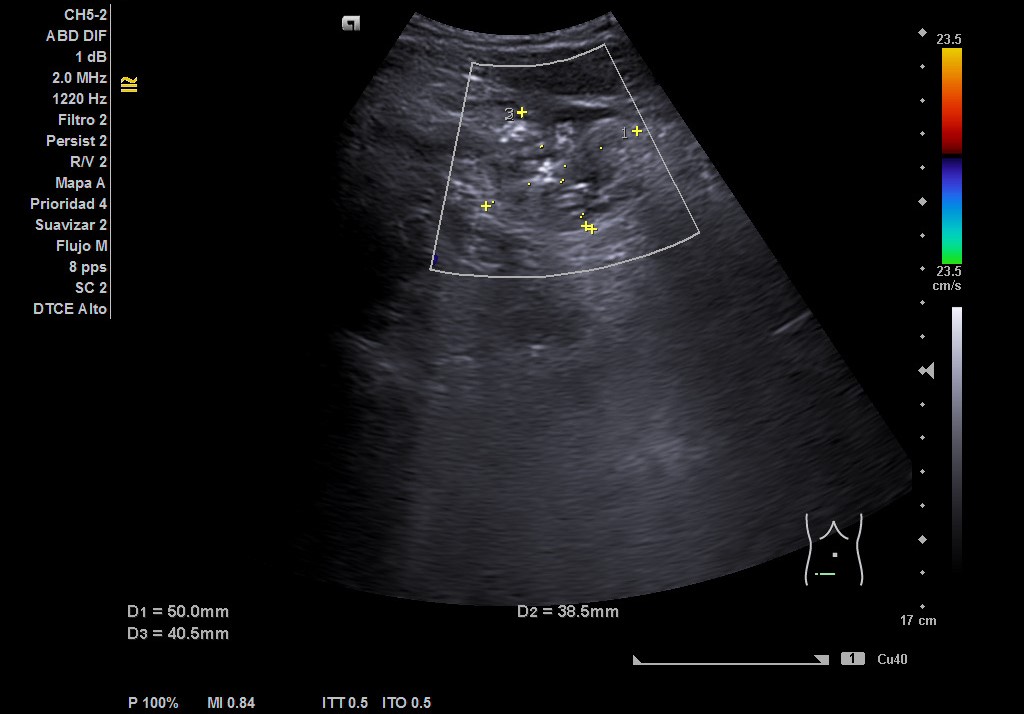

Hígado de tamaño, forma y ecoestructura conservadas, con parénquima homogéneo. Vena porta de calibre conservado.  Ausencia de signos de dilatación de la vía intra o extrahepática. Vesícula biliar de paredes finas, sin contenido ecogénico en su interior. Páncreas de características normales. Riñones de tamaño y localización conservada, sin hidronefrosis. En FID imagen heterogénea delimitada, de 50x30 mm, con posible edema de pared y focos ecogénicos en su interior.

Complicaciones post-quirúrgicas (Plastrón inflamatorio vs absceso). Diagnóstico diferencial: Diverticulitis colon derecho. Tras ecografía realizada por Radiología en el servicio de Urgencias y valoración por Cirugía General se llegó al diagnóstico de plastrón inflamatorio y colección postapendicectomía.